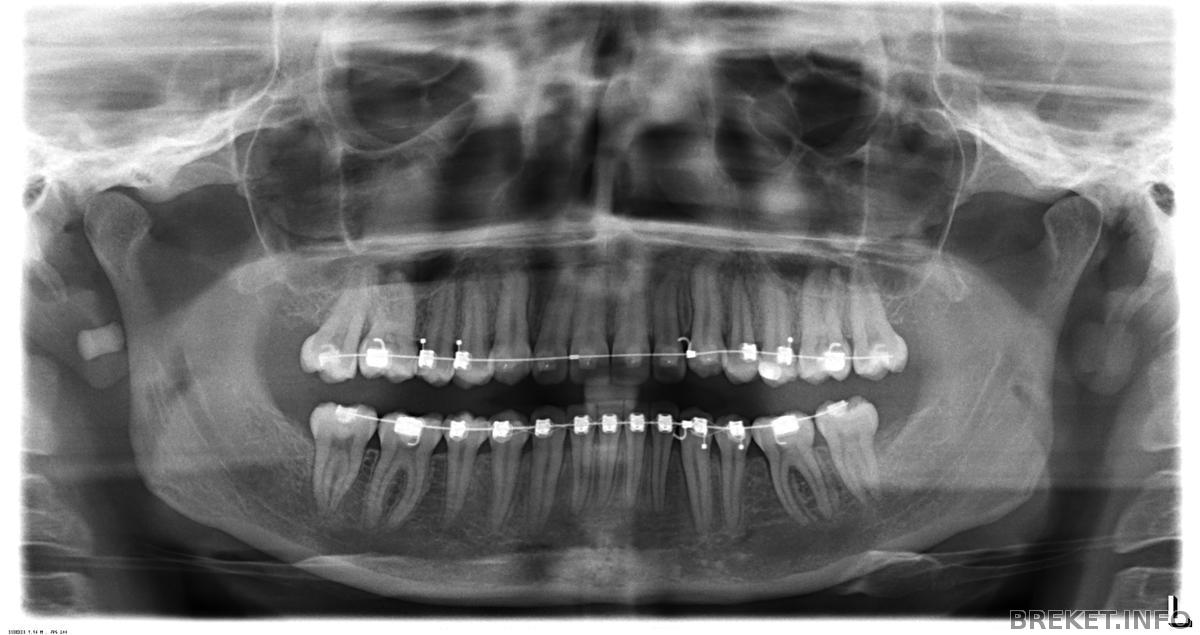

прошло 2 года 6 месяцев, фух, неужели дожила?!

Соответственно, двадцать четыре месяца - НЧ